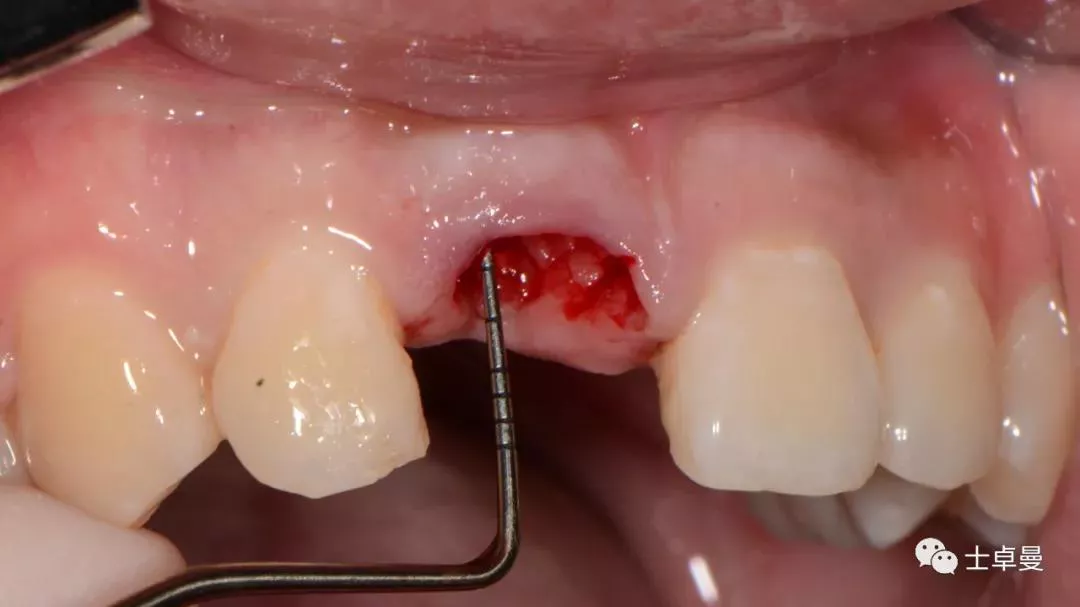

保留唇侧牙片

牙周探针探查牙片位置及松动度

就位种植外科导板

指示杆观察备孔三维位置